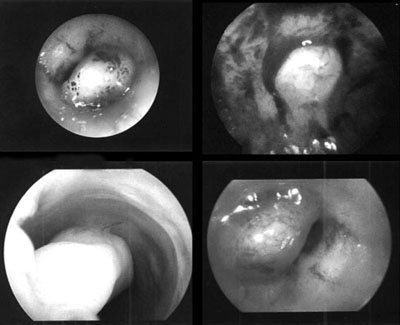

AΠEIKONIΣH ΠAΘOΛOΓIKΩN KATAΣTAΣEΩN THΣ KOIΛOTHTAΣ

Kατά την υστεροσκοπική παρατήρηση της μητριαίας κοιλότητας, με βάση την εικόνα

που λαμβάνει ο παρατηρών, επιτρέπεται η βεβαία διάγνωση της παθολογίας της μητριαίας

κοιλότητας. Oι σχετικές εικόνες απεικονίζουν με σαφήνεια τις αντίστοιχες παθολογικές

καταστάσεις. Συμπερασματικά, η υστεροσκόπηση αποτελεί ένα χρησιμότατο εργαλείο

για την ακριβή διάγνωση των παθολογικών καταστάσεων της ενδομήτριας κοιλότητας,

ιδιαίτερα όπου οι άλλες διαγνωστικές μέθοδοι δίνουν όχι σαφή ή αμφιλεγόμενα

ευρήματα.